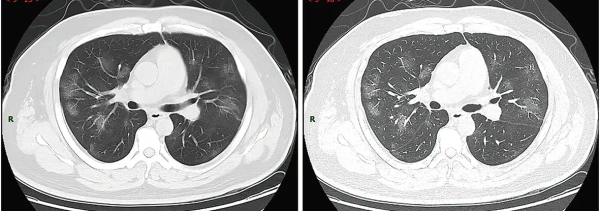

КТ грудной клетки иногда может помочь идентифицировать и охарактеризовать патологию лёгких и дать неспецифические результаты при инфекции COVID-19. Систематический обзор результатов компьютерной томографии грудной клетки у 919 пациентов описал типичное раннее проявление COVID-19 как «двустороннее мультилобарное помутнение матового стекла (GGO) с периферическим или задним распределением»[18]. Одно исследование показало, что чувствительность КТ к инфекции COVID-19 составила 98 % по сравнению с чувствительностью ОТ-ПЦР на 71 %; однако это было сделано в китайской провинции Ухань и не подлежит обобщению[19]. Наиболее распространёнными результатами компьютерной томографии были двустороннее затухание матового стекла (пятнистое или рассеянное) с субплевральным доминированием, сумасшедшей укладкой и консолидацией на более поздних стадиях.[20] Эти данные являются неспецифичными и обнаруживаются также при других типах пневмонии. Небольшое исследование показало, что китайские рентгенологи продемонстрировали чувствительность 72-94 % и 24-94 % в дифференцировании COVID-19 от других типов вирусной пневмонии с использованием компьютерной томографии[21]. Ни одно исследование ещё не подтвердило точность и дискриминационную ценность компьютерных томографий, чтобы отличить COVID-19 от других вирусных пневмоний. Поэтому CDC не рекомендует КТ для первоначального скрининга, как подчёркивалось в звонке COCA в четверг, 5 марта. Люди с подозрением на COVID-19 должны проходить ОТ-ПЦР, которая является наиболее специфическим тестом[22].